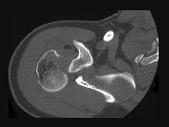

问题 男,28岁,摔伤后肩部疼痛,活动受限,结合影像学表现,最可能的诊断是?(?)

选项 A.柯莱斯骨折 B.肱骨头骨折 C.肱骨外科颈骨折 D.加莱阿齐骨折 E.蒙泰贾骨折

答案 B